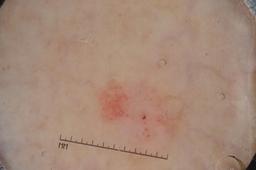

ISIC-DICM-17K (ISIC Dermoscopic Images and Clinical Metadata 17K) is a curated and balanced dataset derived from the International Skin Imaging Collaboration (ISIC) Archive Gallery. It comprises 17,060 dermoscopic images and clinical metadata (8,530 melanoma and 8,530 non-melanoma classes).

For more details, please follow the project’s GitHub repository: https://github.com/mmu-dermatology-research/isic-dicm-17k

This dataset was used in this study and benchmark to explore the effectiveness of multimodal learning for skin lesion classification:

S. Ahammed, X. Cui, W. Lu and M. H. Yap, "Skin Lesion Classification using Dermoscopic Images and Clinical Metadata: Insights from Multimodal Models," 2025 IEEE/CVF Conference on Computer Vision and Pattern Recognition Workshops (CVPRW), Nashville, TN, USA, 2025, pp. 222-230, DOI: 10.1109/CVPRW67362.2025.00027